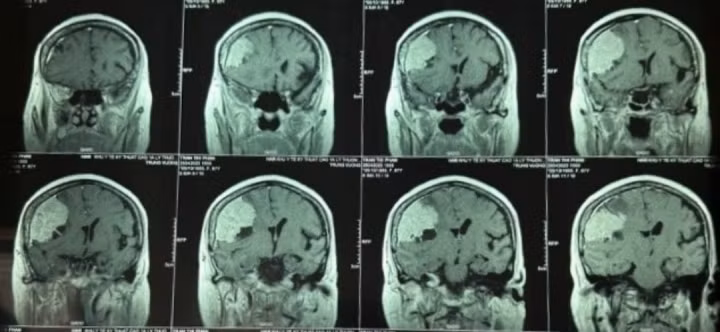

| U màng não to hơn quả trứng vịt. Ảnh VTC News |

Kết quả chẩn đoán phát hiện người bệnh có u màng não lớn vùng thái dương bên phải, có nhiều mạch máu nuôi u. Bác sĩ lên kế hoạch phẫu thuật.

Ngày 16/5, ca phẫu thuật đã lấy toàn bộ khối u màng não có kích thước lớn, to hơn quả trứng vịt. Sau 10 ngày, bệnh nhân hồi phục tỉnh táo, hết yếu liệt, sinh hoạt bình thường.